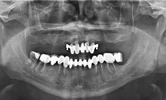

د. عائشة ألينيا يلماز

ألم تحت الأسنان السفلية

د. عائشة أليناء يلماز طبيبة أسنان

الصور